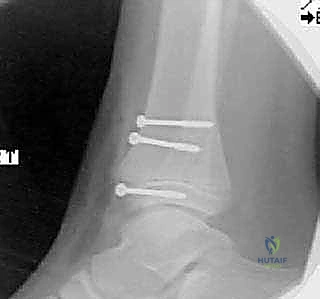

- الأشعة السينية (X-rays): هي الخطوة الأولى والأساسية. يتم التقاط صور من زوايا متعددة (أمامية، جانبية، ومائلة) لتقييم الكسر.

- الأشعة المقطعية ثلاثية الأبعاد (3D CT Scan): تُعد ضرورة حتمية في حالات كسور تيلوكس والكسور ثلاثية المستويات، أو أي كسر يمتد داخل المفصل. توفر الأشعة المقطعية خريطة دقيقة لحجم القطع العظمية ومقدار التباعد (Displacement)، مما يساعد في التخطيط الجراحي المسبق.

ثانياً: التدخل الجراحي (الرد المفتوح والتثبيت الداخلي - ORIF)

يصبح التدخل الجراحي ضرورة طبية لا مفر منها تحت إشراف الأستاذ الدكتور محمد هطيف في الحالات التالية:

* جميع كسور سالتر-هاريس من النوع الثالث والرابع إذا كان هناك تباعد أكثر من 2 ملم في السطح المفصلي.

* كسور تيلوكس والكسور ثلاثية المستويات ذات الانزياح الواضح.

الدليل الجراحي التفصيلي: خطوة بخطوة مع الأستاذ الدكتور محمد هطيف

عندما يقرر الأستاذ الدكتور محمد هطيف إجراء الجراحة، فإن العملية تتم وفق أعلى المعايير العالمية المتبعة في أعرق المستشفيات. الجراحة ليست مجرد "تثبيت بمسامير"، بل هي فن هندسي وطبي متكامل لحماية مستقبل الطفل.

يقوم الدكتور هطيف بعمل شق جراحي دقيق بأقل تداخل ممكن (Minimally Invasive) للوصول إلى موقع الكسر. يعتمد مكان الشق (أمامي، جانبي، أو إنسي) على نوع الكسر. يتم إبعاد الأوتار والأعصاب والأوعية الدموية بحذر شديد باستخدام تقنيات الجراحة الميكروسكوبية.

3. إزالة الأنسجة المتداخلة والرد التشريحي (Debridement & Reduction)

هذه هي الخطوة الأهم. كما ذكرنا سابقاً، غالباً ما يتداخل السمحاق (Periosteum) داخل خط الكسر. يقوم الدكتور هطيف بإزالة هذا السمحاق المتداخل برفق، وتنظيف موقع الكسر من أي جلطات دموية أو شظايا عظمية صغيرة. بمجرد تنظيف الموقع، يتم إعادة القطع العظمية إلى مكانها الطبيعي بد